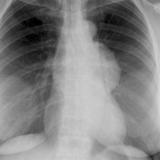

Case 8a Thymoma PA

Date: 03/27/2009

Views: 9543